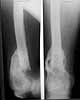

A male 53 years old Nov. 25, 2002 sustained multiple injuries including pelvic ring lesion, # of the left acetabulum, # of the right femoral shaft, left patella, also left ankle and right forearm. He was initially treated elsewhere on traction, the ankle in plastre cast and the forearm with ex-fix.

At the opposite side (right) there is femoral malunion, lack of full knee extension though the extremity is weight-bearable. Shortening is 3 cm.

1. I would take down right femur nonunion and correct translation (it looks at very high risk to refracture), shortening and mild flexion deformity (these latter two corrections look like they would gain at least 1 cm of length.